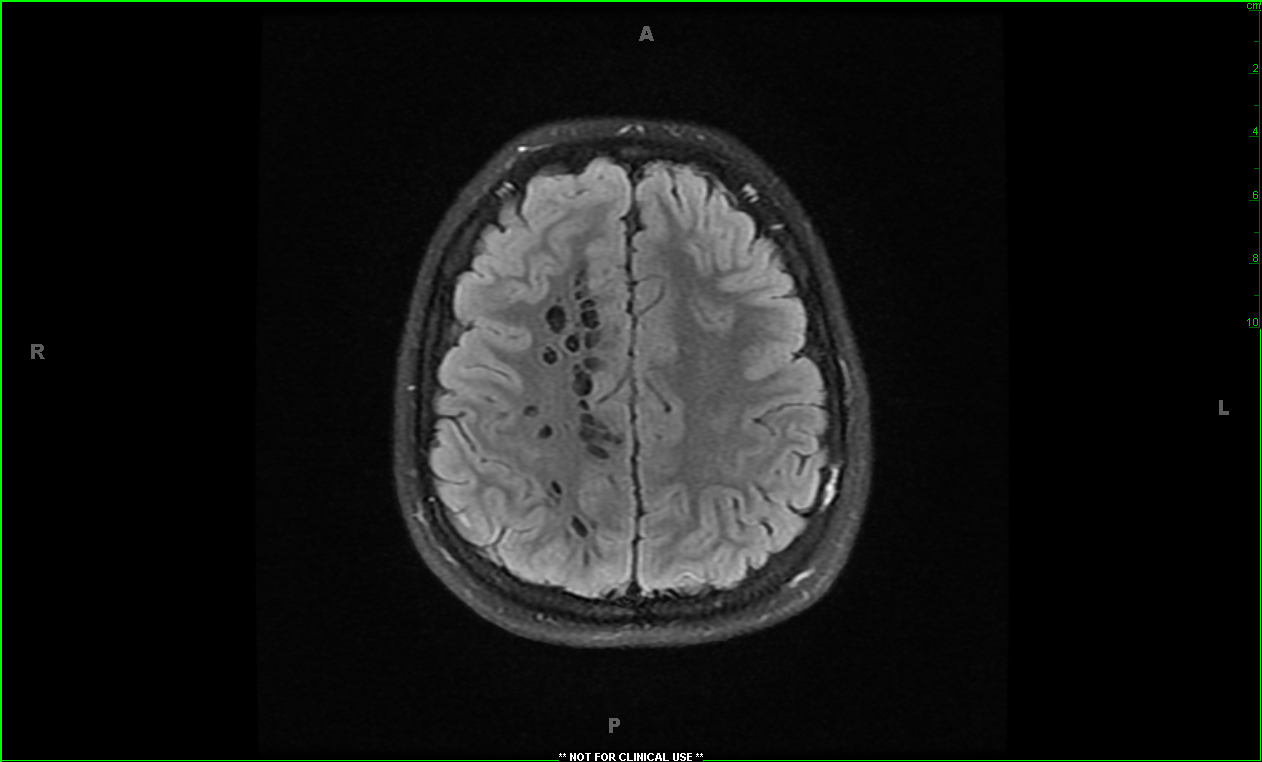

An 11 year old boy with a headache

What is the finding on this CT?

This patient had enlarged Virchow-Robin spaces. These are spaces between an artery or vein and the pia mater which can dilate in various conditions. They can be filled with WBCs in viral encephalitis and interstitial fluid/csf  in the case of dementia, stroke , multiple sclerosis or autism.

neurocysticercosis  can have a similar appearance

Things that can look similar on CT or MRI include:  neurocysticercosis, cryptococcosis, lacunar infarcts ,cystic neoplasms, MS and mucopolysaccharidoses.

In our patient , the Virchow-robin space dilation was thought to be benign and no further workup was done.